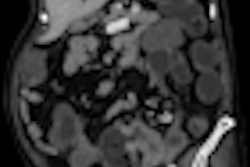

The team found that reconstructed shear stiffness maps appear smoother and more uniform using the piezoelectric system. Despite having noisier maps, the pneumatic system still produces results that are consistent with the results obtained with the piezoelectric setup.